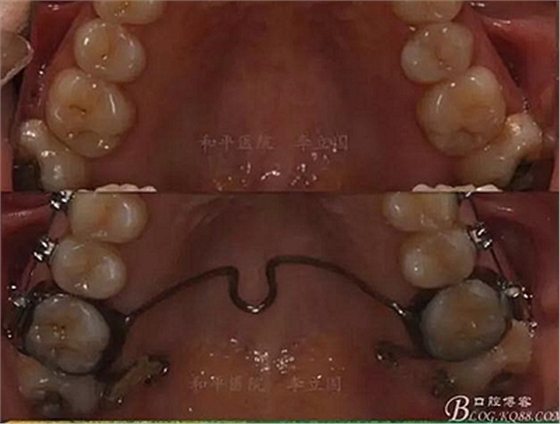

該病例主要為17、27頰側(cè)位同時伴有伸長,當(dāng)然種植支抗可以解決,但還有簡單實(shí)用的辦法嗎?如圖,在橫腭桿遠(yuǎn)中延伸出牽引鉤,位置盡量遠(yuǎn)離合平面,7粘舌側(cè)扣,牽引力的方向?yàn)閴旱图吧嘞?,下圖為兩個月的效果,17已到位,27還未到位。